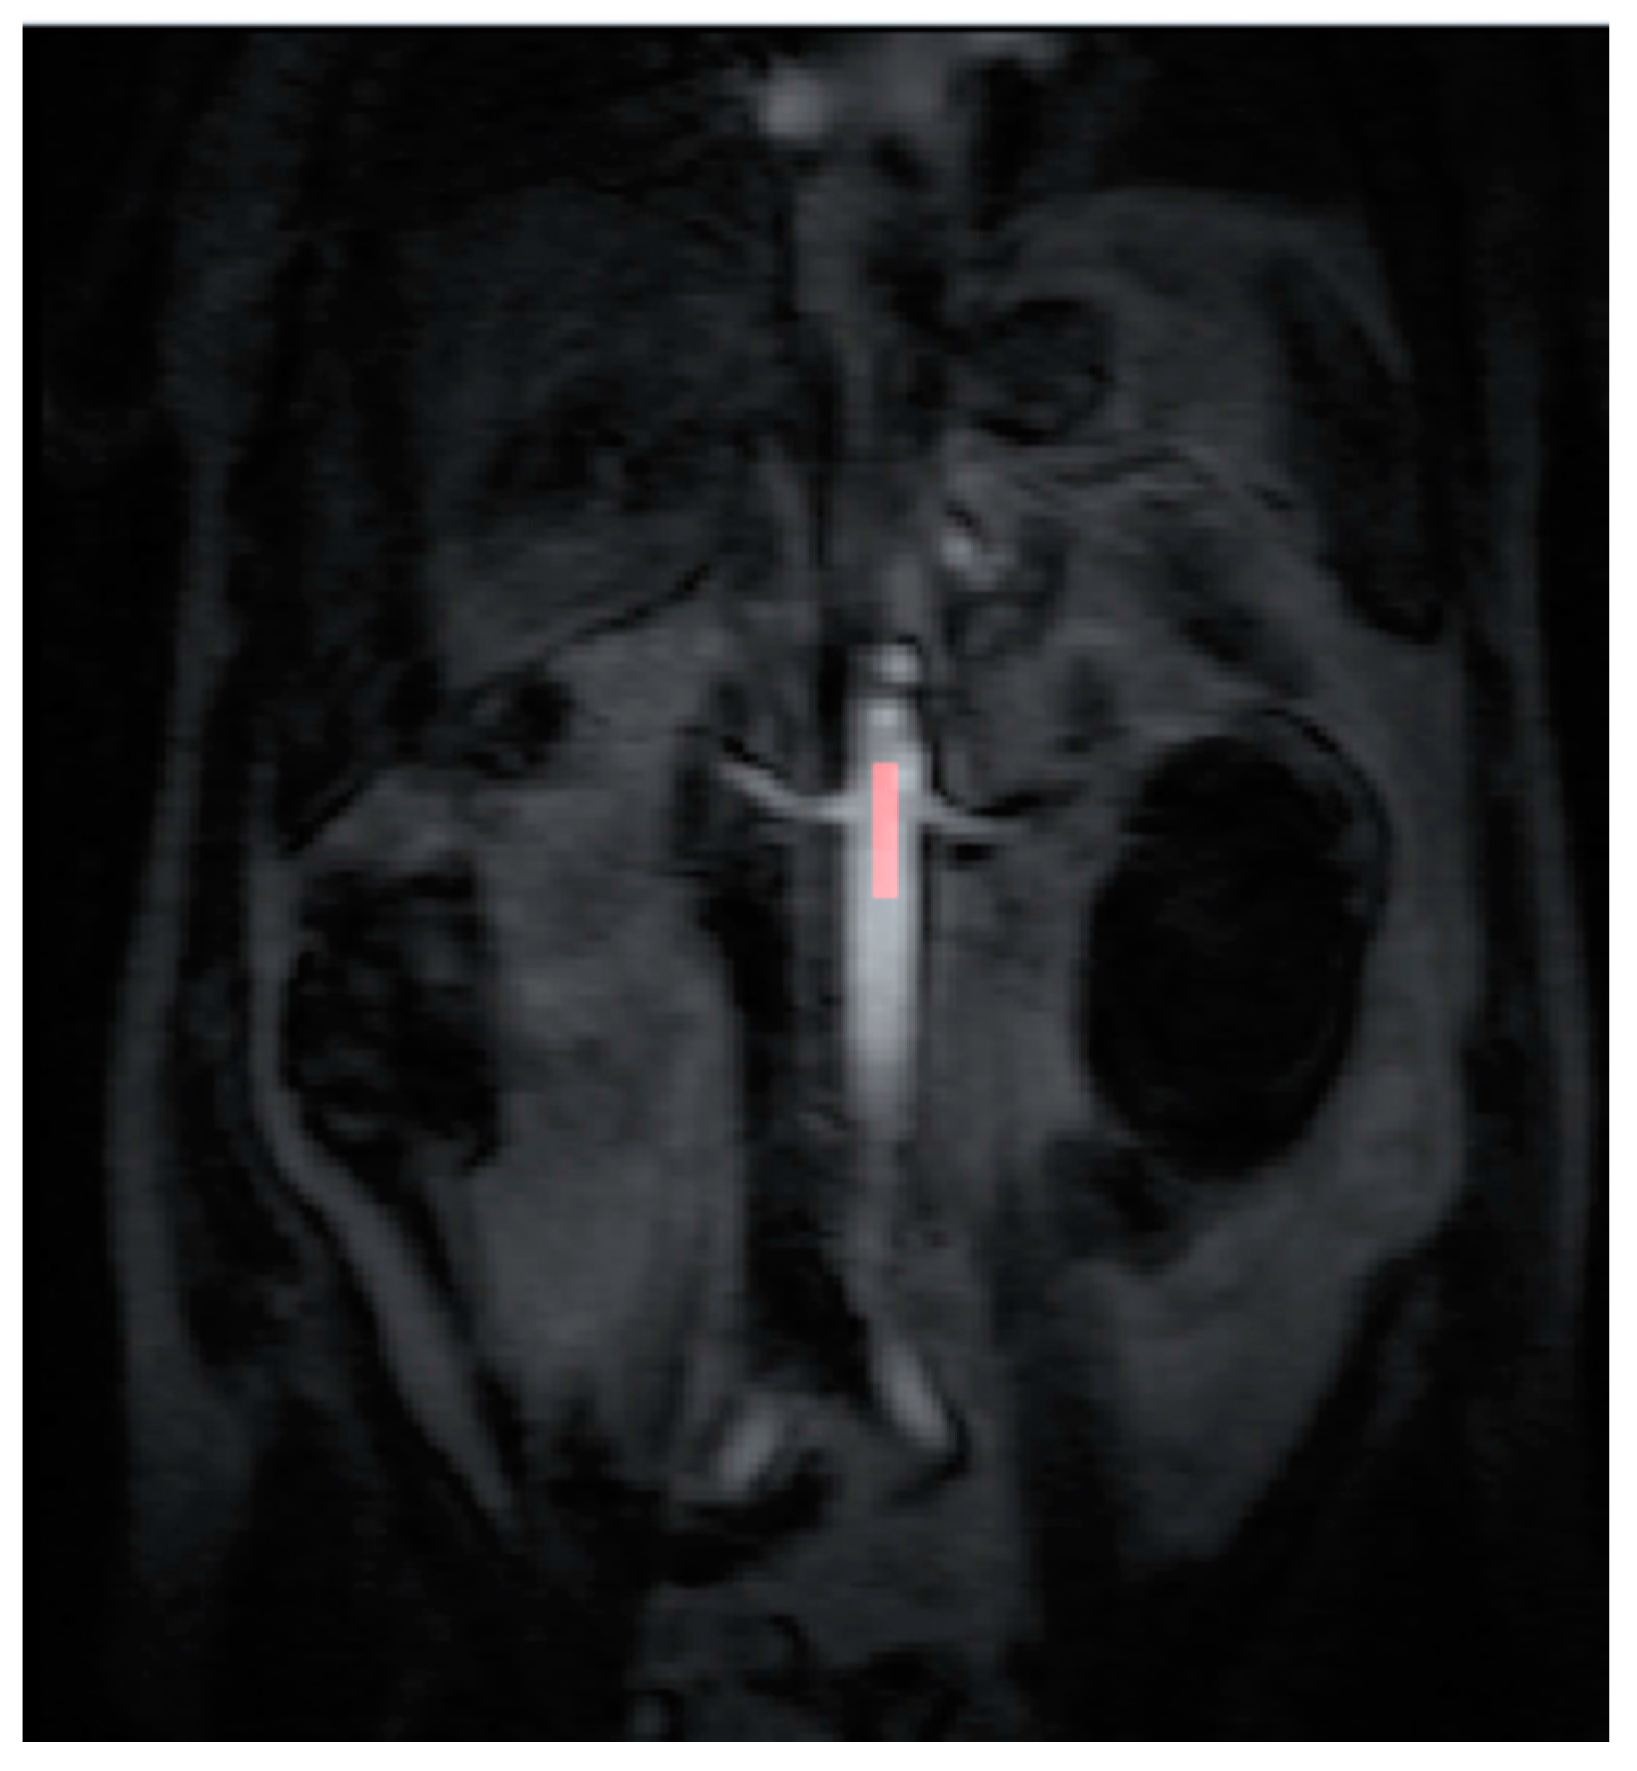

2.4. Data Post Processing

All the MR images were anonymized and post processing was performed offline by a single consultant radiologist with greater than 10 years of clinical experience (Dr Tze Min Wah). Images were uploaded into PMI 0.4 (Platform for Research in Medical Imaging Version 0.4 [13], which was running on a desktop PC. A standardized 4-voxel region was used to extract an arterial input function (AIF). This region of interest (ROI) was drawn inside the aorta at the approximate level of the origin of the vascular pedicles of the kidneys (Figure 1 and Figure 2).

Figure 1. The arterial input function (AIF) region of interest (ROI) was drawn inside the aorta at the approximate level of the origin of the vascular pedicles of the kidneys in the dynamic series.